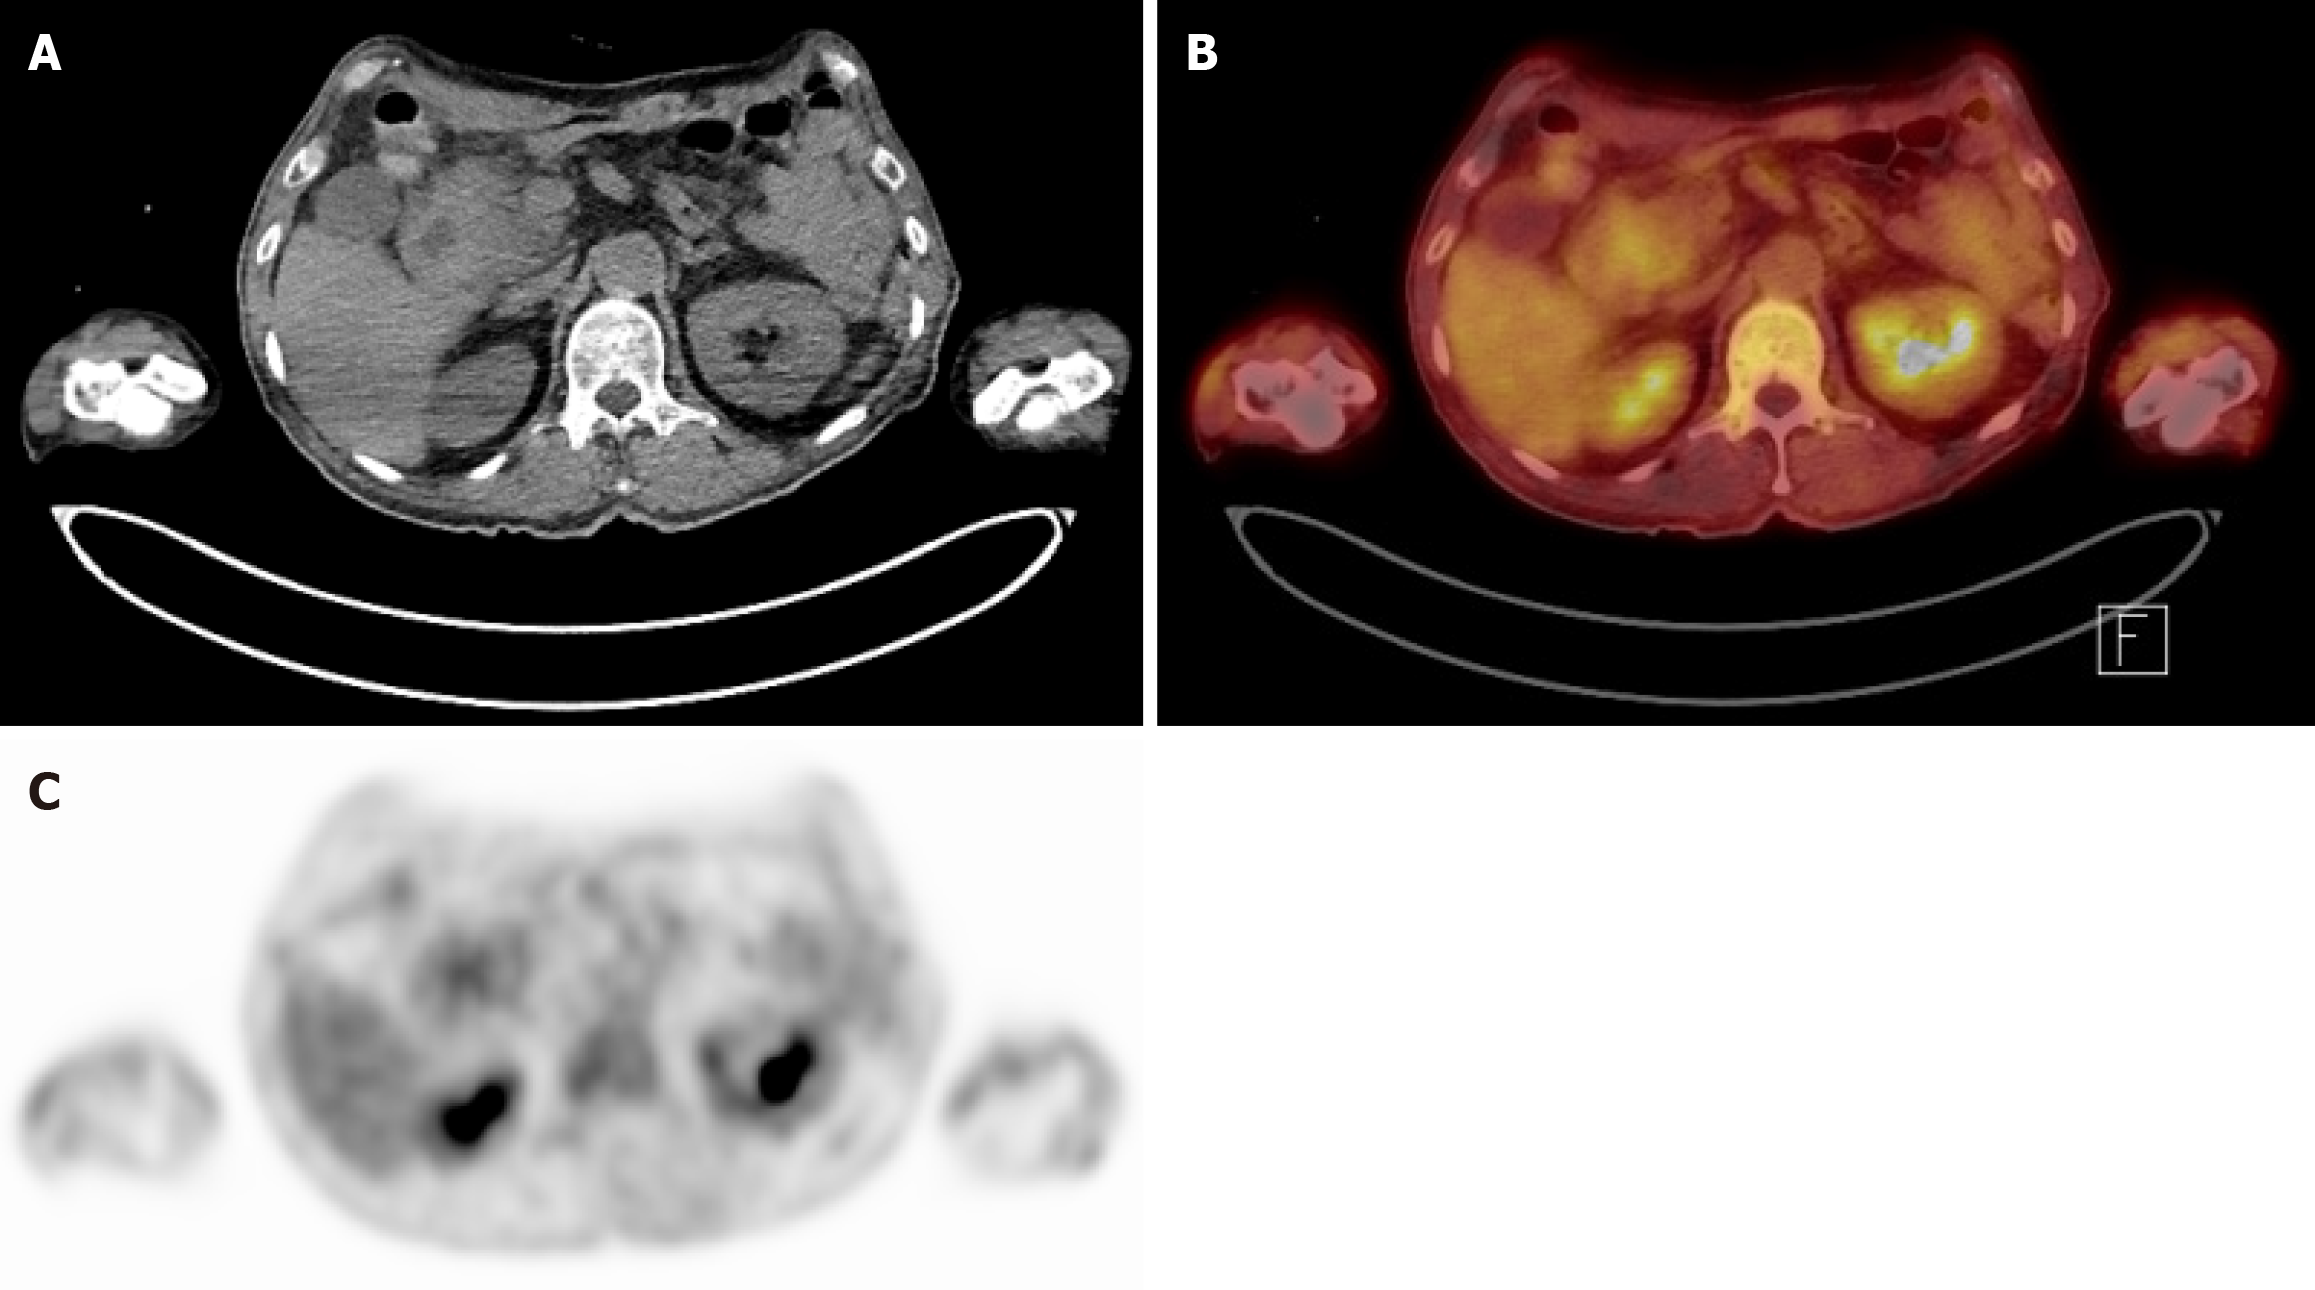

Figure 4 Positron emission tomography-computed tomography images.

A: Axial computed tomography torso image. Mass at periampullary area; B: Fusion positron emission tomography-computed tomography image demonstrating a mild hypermetabolic mass-like lesion in the second portion of the duodenum near the ampulla of Vater of unknown clinical significance; C: Axial positron emission tomography image showing the corresponding focal uptake in the same region of (B).